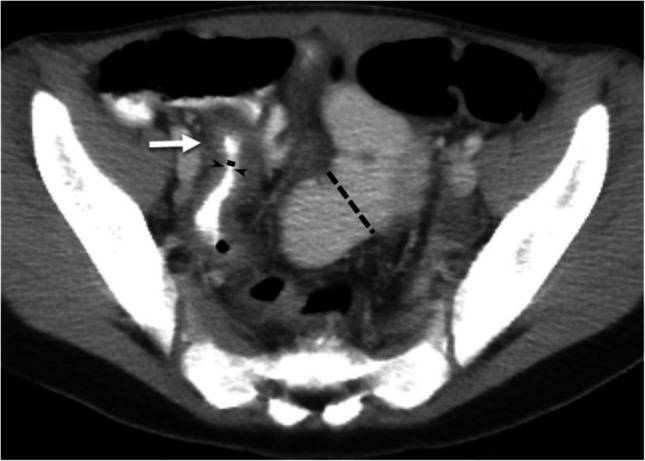

背景:横断面成像越来越多地用于克罗恩病的初始诊断和长期监测。回肠末端的定量形态学可以预测治疗效果。目的:我们旨在确定与克罗恩病儿童大队列临床和放射学治疗反应相关的基线定性和定量影像学特征。材料和方法:这是一项针对儿童克罗恩病的风险队列研究的回顾性研究。本多中心研究纳入1136名儿童。结果:纳入96名受试者。38% (n=36)的参与者达到了临床缓解终点,只有20% (n=19)的参与者达到了影像学正常化。随访影像显示24例(25%)患者疾病进展,其中7例(7%)在基线时放射学正常(7%)。较高的基线TI分类评分与随访期间影像正常化的几率较低相关(OR 0.4 [0.2, 0.8], P=0.009)。较大的TI最小管腔直径(OR 1.1 [1.01, 1.3], P=0.04)和较小的基线肠壁最大厚度(OR 0.8 [0.6, 0.97], P=0.03)与影像学正常化相关。没有与临床反应相关的基线影像学测量。结论:基线回肠末端最小管腔直径增加和壁厚减少与随访时的影像学正常化有关,但与临床反应无关。

Materials and methods: This was a retrospective study of the RISK cohort study in pediatric Crohn's disease. This multicenter study included 1,136 children <18 years from 28 sites in North America. Subjects enrolled with newly diagnosed Crohn's disease who underwent endoscopy with baseline and follow-up CT or MRI were considered for this study. Exclusion criteria were incomplete data or surgical resection prior to follow-up imaging. Imaging analysis included assessing a qualitative terminal ileum (TI) categorical score based on SAR-AGA consensus definitions ((1) normal, (2) inflammation only without luminal narrowing, (3) inflammation with luminal narrowing, or (4) stricture with pre-stenotic dilation ≥3 cm) and quantitative measurements (maximum bowel wall thickness and maximum/minimum lumen diameter). Two endpoints were considered: (1) clinical response (off corticosteroids and quiescent Physician Global Assessment at follow-up imaging) and (2) CT and MRI response (follow-up imaging normalization). Multivariable logistic regression analyses were developed for each endpoint.

Results: Ninety-six subjects were included. Clinical response endpoint was achieved in 38% (n=36) of participants, and imaging normalization was achieved in only 20% (n=19) of participants. Follow-up imaging showed disease progression in 24 (25%) patients, 7 (7%) of whom were radiologically normal at baseline (7%). A higher baseline TI categorical score was associated with lower odds of imaging normalization during follow-up (OR 0.4 [0.2, 0.8], P=0.009). Larger TI minimum lumen diameter (OR 1.1 [1.01, 1.3], P=0.04) and smaller maximum bowel wall thickness at baseline (OR 0.8 [0.6, 0.97], P=0.03) were associated with imaging normalization. There were no baseline imaging measurements associated with clinical response.